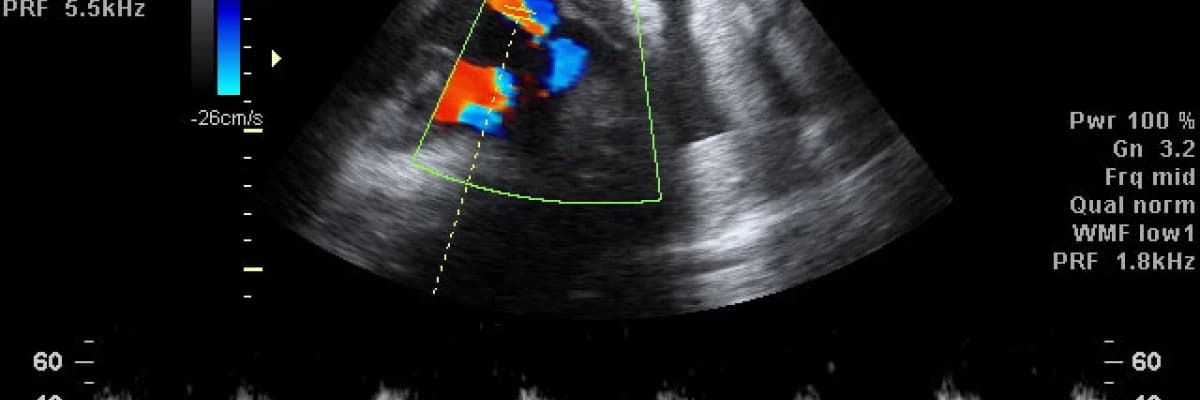

Doppler genel anlamda ultrason altında incelenen damar yatağının kan akımını ve normal dışı bir dirençle karşı karşıya olup olmadığını belirleyen bir testtir. Halk arasında ‘’renkli ultrason’’ olarak bilinen ultrason çeşidi budur ve amaç bebeği renkli olarak görüntülemek değil kalbin sistol (atım) ve diyastol (dolum) zamanlarında “kan akım hızlarını” incelemektir.

Kalbin atım ve dolum fazında incelenen damar yatağındaki basınçlar karşılaştırarak direnç belirlenir. Obstetrik (gebelikle ilgili) uygulamalarda anneden bebeğe kan götüren uteroplasental üniteyi değerlendirebileceği gibi, bebeğin kordonun kan akımı konusunda bilgi verir. Böylece ileride ortaya çıkabilecek gebelik zehirlenmesi (preeklempsi), rahim içi gelişme geriliği, plasentanın erken ayrılması (ablasyo plasenta), anne karnında bebek ölümü gibi durumlar açısından artmış riskler öngörülebilir.

Gebeye yapılan rutin ultrason incelemesinden sonra önce sağlı sollu uterin arterlerde, sonra da umbilikal (kordon) arterde doppler incelemesi yapılır. Her iki uterin arterin akım değerleri, ikisi arasındaki matematiksel fark ve görünüm şekilleri değerlendirilir. Umbilikal arterde de yine akım değerlendirilir ve dalga şekli incelenir.

Doppler tanı koydurucu değil yönlendirici bir testtir. Patolojik akım değerleri ya da anormal dalga görünümleri elde edildiğinde bebeğin diğer iyilik hali testleriyle yakından değerlendirilmesi konusunda hassas olunması gerektiğini gösterir. Bunun tek istisnası umbilikal arterde "ters akım" denen bir durumun ortaya çıkmasıdır. Umbilikal arterde bu anormal dalga şekli gözlendiğinde bebeğin karında ölme riski oldukça yüksektir ve acil doğum gerekebilir.